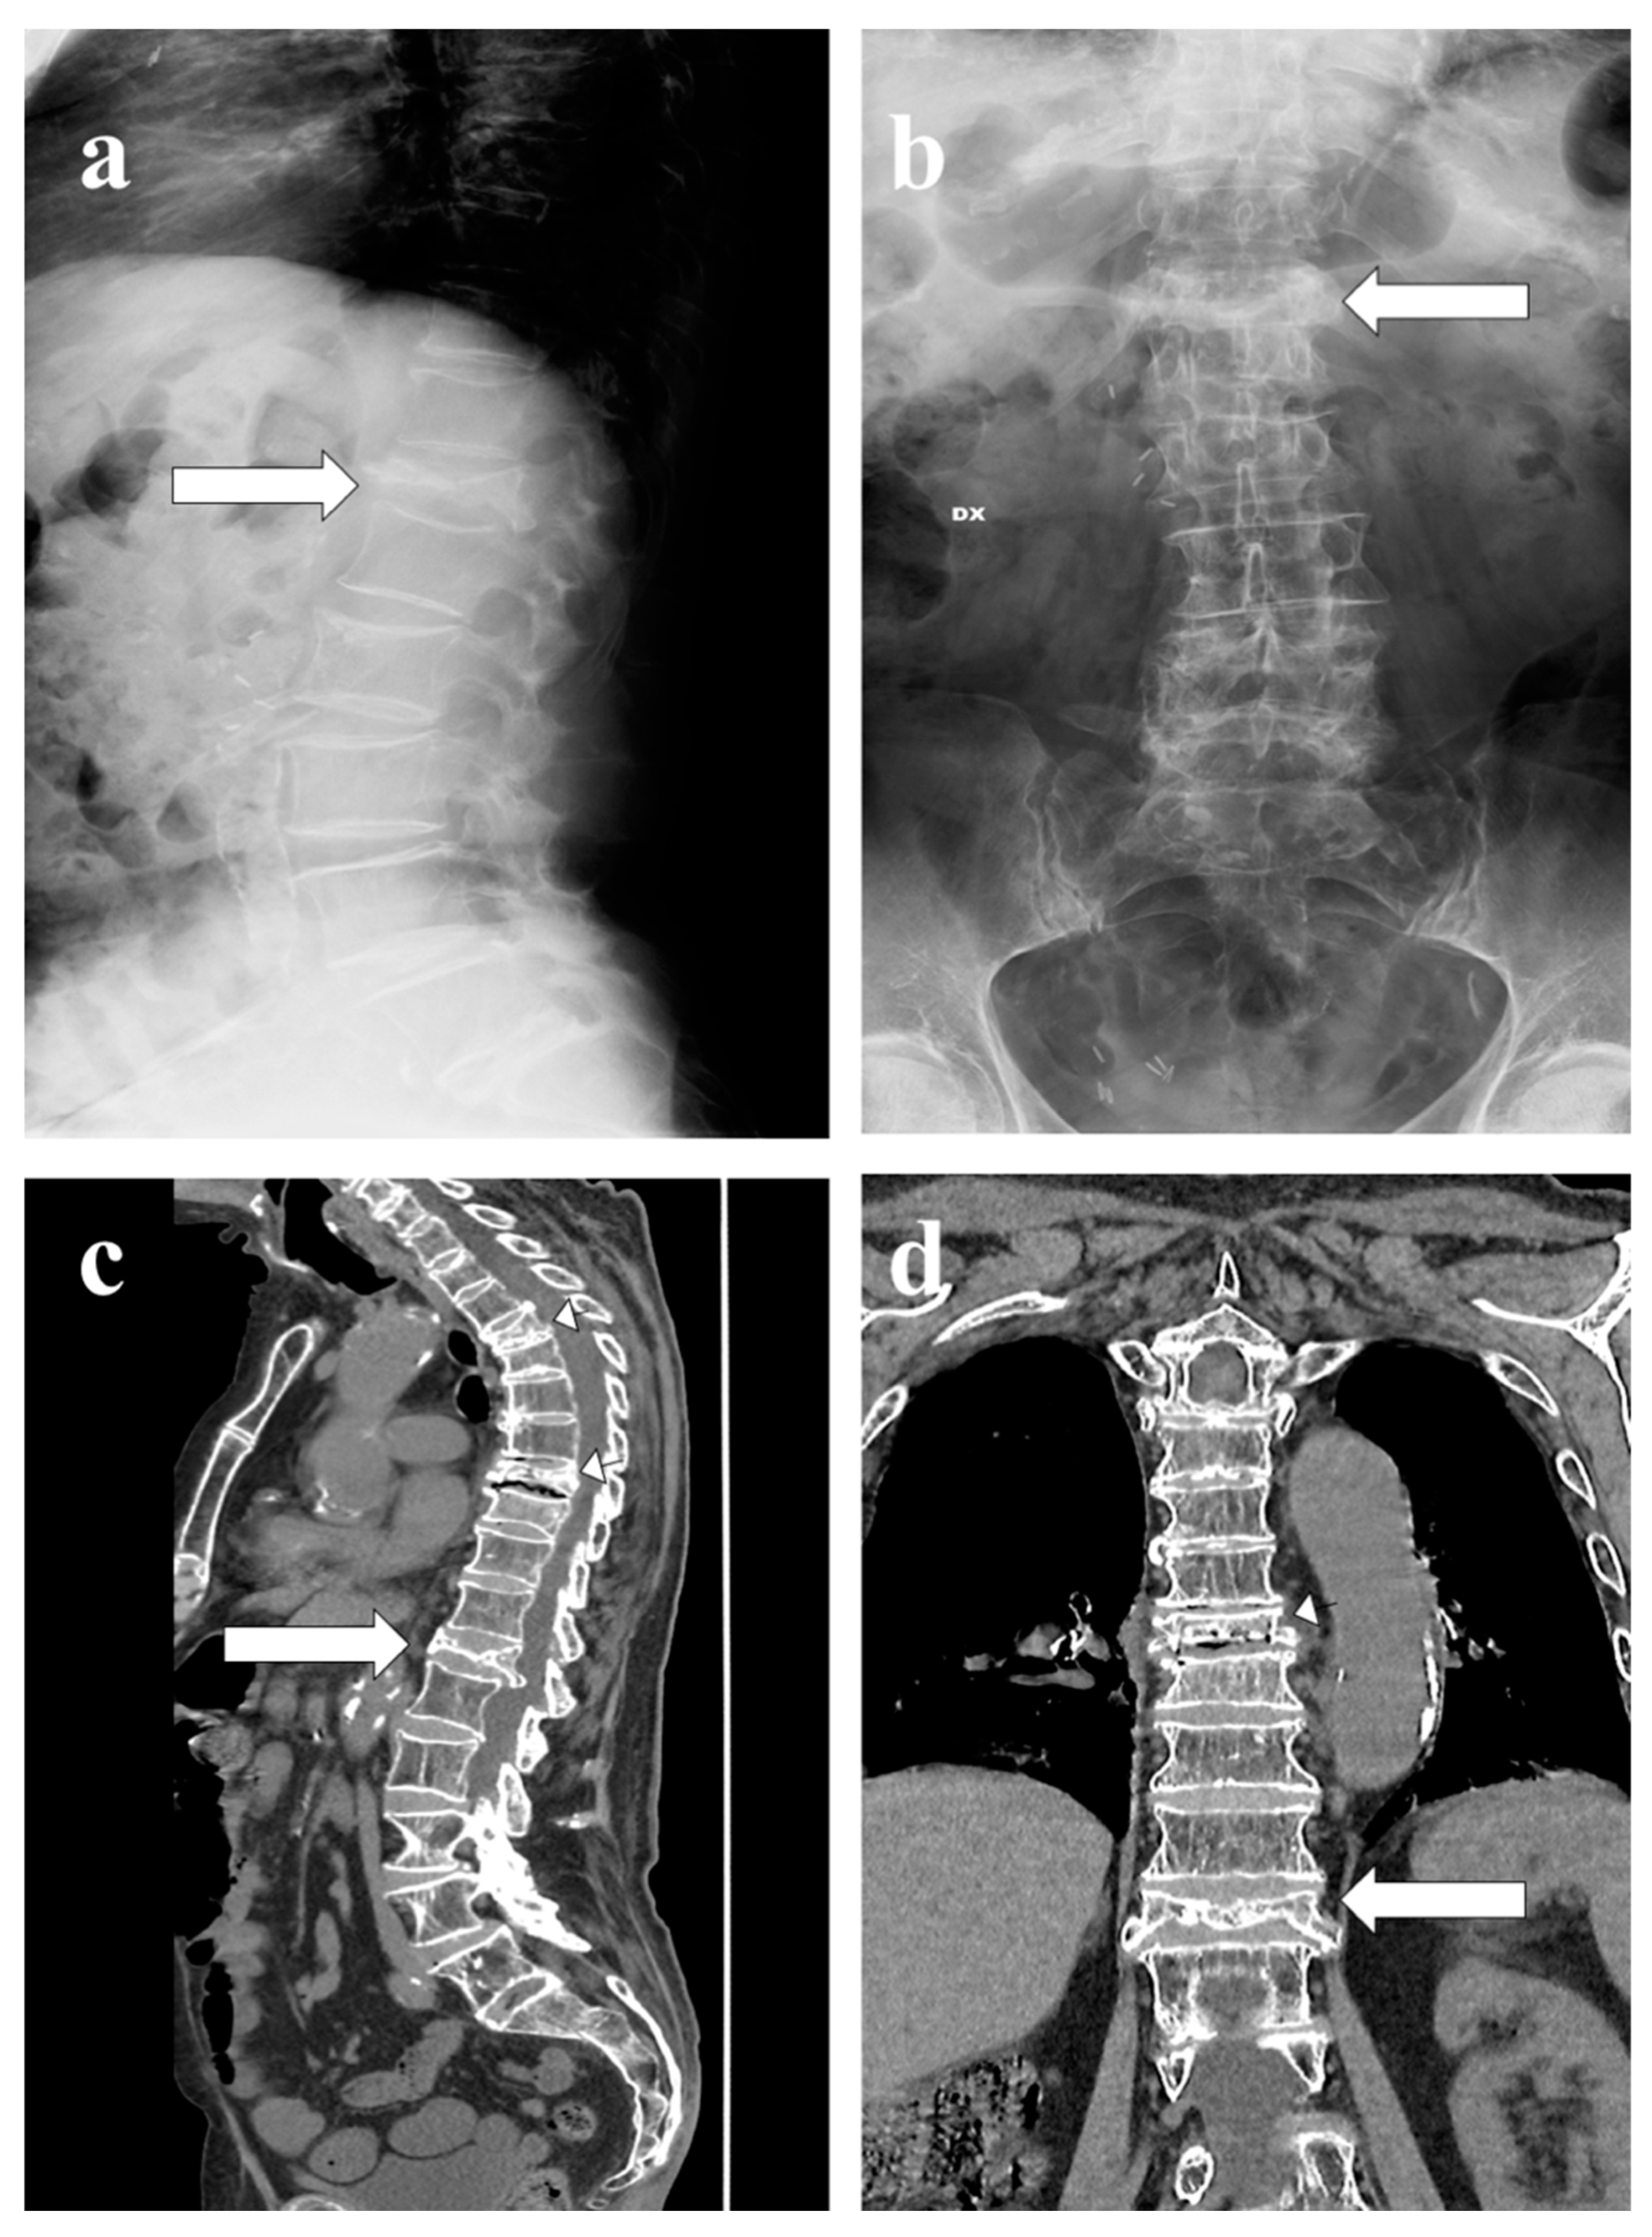

- Sureka, J.; Samuel, S.; Keshava, S.; Venkatesh, K.; Sundararaj, G. MRI in patients with tuberculous spondylitis presenting as vertebra plana: A retrospective analysis and review of literature. Clin. Radiol. 2013, 68, e36–e42. [Google Scholar] [CrossRef]